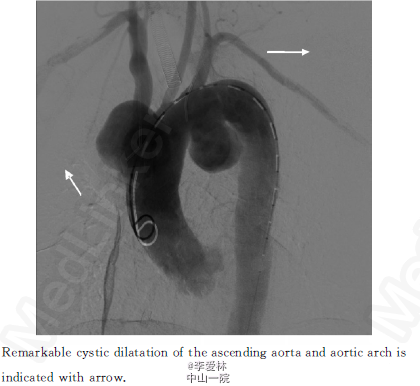

心超(上海长征医院2013年3月18日)升主动脉远端及主动脉弓起始部瘤样扩张,主动脉壁粗糙,轻度肺动脉高压伴三尖瓣返流。全主动脉CTA:升主动脉及主动脉弓见多发瘤样膨出,扩张管径分别为49.1、33.9和19.2 mm,全主动脉管壁内见软硬斑块,部分见钙化影见